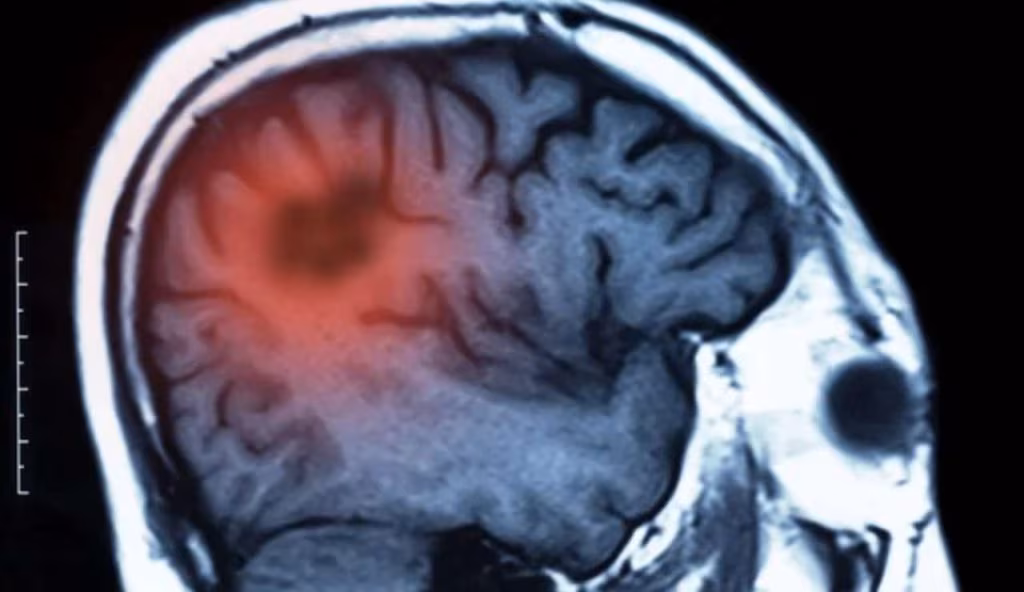

Tumore cerebrale (Depositphotos foto) - www.biomedicalcue.it

Come i tumori cerebrali riescono a ingannare il sistema immunitario, trasformando le sue cellule in alleati per la loro crescita.